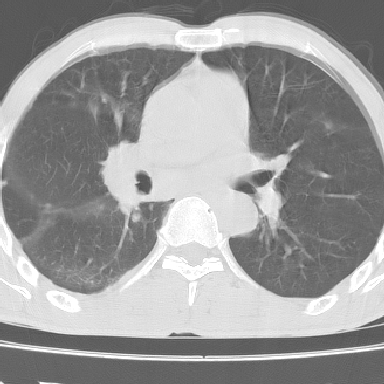

以下是引用lpc0ct在2006-11-28 16:12:00的发言:[br]大家图文并貌分析的太全面了,没有可说的,同意 [br] 右肺上叶中心型肺癌伴肺门、纵隔淋巴结转移.[br]

以下是引用dyqct在2006-11-28 16:00:00的发言:[br]右肺上叶中心型肺癌伴肺门、纵隔淋巴结转移。[br][br]